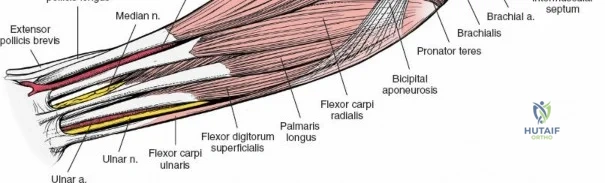

The anterior approach to the radius is an elegant example of utilizing true internervous planes to achieve deep exposure without denervating musculature. Distally, the internervous plane lies between the brachioradialis muscle (innervated by the radial nerve) and the flexor carpi radialis muscle (innervated by the median nerve). Proximally, the plane transitions to lie between the brachioradialis (radial nerve) and the pronator teres muscle (median nerve). Exploiting this plane allows the surgeon to mobilize the entire lateral muscular compartment (the "mobile wad" comprising the brachioradialis, extensor carpi radialis longus, and extensor carpi radialis brevis) away from the anterior flexor compartment.

Accurate identification of surface landmarks is the first step in a successful Henry approach. Palpate the biceps tendon, a stout, taut structure crossing the anterior elbow joint just medial to the brachioradialis muscle. Next, palpate the brachioradialis itself, the fleshy muscle forming the lateral border of the cubital fossa. Finally, identify the styloid process of the radius distally. Note that when the forearm is fully supinated (the anatomic position), the radial styloid is truly lateral.

Superficial Surgical Dissection and Internervous Plane

Incise the deep fascia of the forearm in line with the skin incision. The initial goal is to identify the medial border of the brachioradialis as it courses down the forearm. It is a common pitfall to search for this border too far laterally. At the level of the elbow, the brachioradialis is expansive and extends almost halfway across the anterior forearm. It is surprisingly easy to mistake the plane between the brachioradialis and the extensor carpi radialis longus for the correct intermuscular plane.

To confirm the correct plane, look for the superficial branch of the radial nerve. This sensory nerve runs on the undersurface of the brachioradialis muscle. Once the true medial edge of the brachioradialis is found, develop the plane between it and the pronator teres (proximally) or the flexor carpi radialis (distally). Retract the brachioradialis laterally, taking care to keep the superficial radial nerve attached to its undersurface to protect it from traction injury.

Exposing the proximal third of the radius requires extreme vigilance due to the proximity of the posterior interosseous nerve. The key anatomical landmark here is the insertion of the biceps tendon. Follow the biceps tendon distally to its insertion on the bicipital tuberosity of the radius. A small bursa lies just lateral to the tendon; incise this bursa to gain initial access to the proximal radial shaft. Because the radial artery lies superficial and medial to the tendon at this level, all deep dissection must remain strictly lateral to the biceps tendon.